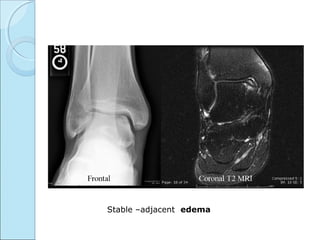

Stable –adjacent edema

Stable OCD –coronal & sagittal T2W shows lesion of

medial condyle and marrow edema .